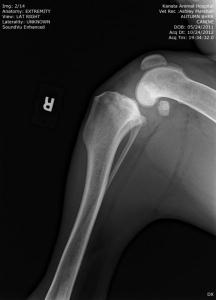

UPDATE: I know I have much to update in BHRR's Autumn's blog and before I go to bed in the wee hours; I shall update her blog plus add photos from her x-rays – taken of both legs, chest, back, legs, heart etc. on October 24th, 2012 and you can find them below! 🙂

From there, we are putting our creative hats on as she will need two cruciate surgeries – $6,000-$7,000+ – and the specialist is still looking at those eyes and what is going to be best….

She has three surgeries ahead of her – a spay and two separate cruciate surgeries and this is in addition to her almost $3,000 bills to date that have been racked up.